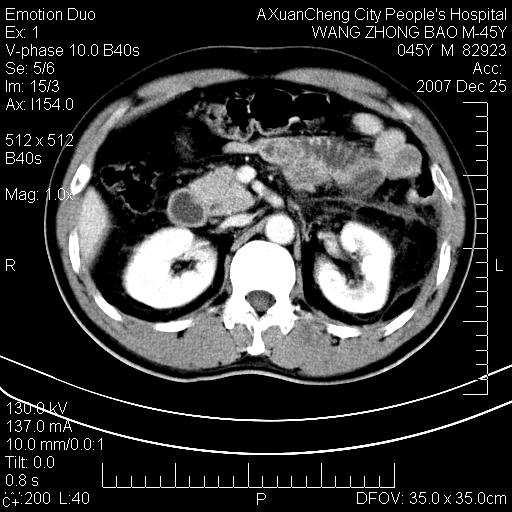

以下是引用qiuleiyu在2007-12-25 18:14:00的发言:[br]胰腺增大,周边渗出改变,肾前筋膜明显增厚,示少量积液.胆囊壁毛糙,周边少许渗出,胆总管壁厚,异常强化,然扩张不明显.结合病程急短;考虑;胆管炎,胆囊炎,胆源性胰腺炎可能大,请结合实验室检查及随访.

以下是引用lisihao在2007-12-25 14:23:00的发言:[br]急性水肿型胰腺炎[br]依据:1、胰腺弥漫性肿大,边缘稍毛糙;[br] 2、双侧肾周筋膜增厚,尤以左侧为甚(重要征象)[br] 3、双侧后胸膜增厚(刺激性炎症);[br] 4、结合病史,查血尿淀粉酶应该可以确诊。